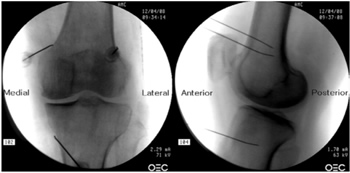

Figura 1

Figura 2

Figura 3

Figura 4

Figura 5